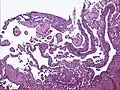

Low power photomicrograph of an endovascular papillary angioendothelioma showing papillae with hyalinized cores

High power view showing a vascular tumor with cuboidal endothelium lining the vessels. Few entrapped seminiferous tubules are also noted (arrow).- Characteristic budding, hobnail-like endothelial cells visible.